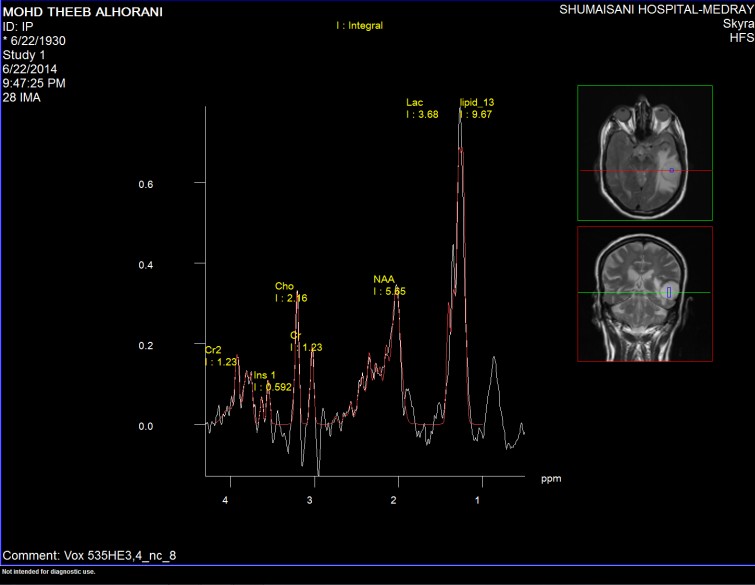

Spectroscopy was done the day before surgery, supporting data for MTS (Figure1-6).

Fugure-3: Choline distribution using short TE 2D CS.

Figure-4: NAA distribution using short TE 2D CS.

Figure-5: Elevated LIP 13 and LIP 09 inside the lesion using short TE 2D CS.

Figure-6: Lipid 13 distribution  using short TE 2D CS.